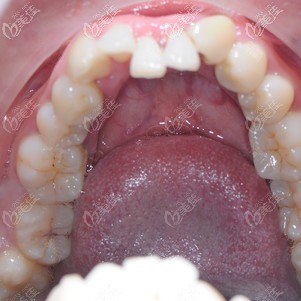

術(shù)前照片:

術(shù)后照片:

兩顆下門牙往里凹的還挺明顯,不光咬合不正常,露牙笑的時候也不美觀,本來早就想做矯正,但心里還是有點(diǎn)擔(dān)心和排斥,所以湊合了這么長時間。

我做的是時代天使牙齒矯正,花了1萬多,感覺還可以接受。拍完片后,醫(yī)生說我的其他牙齒排列不齊,影響咬合,長期下去其實(shí)不利于牙齒的健康,所以這次都可以一起矯正,但是要配合醫(yī)生的工作。